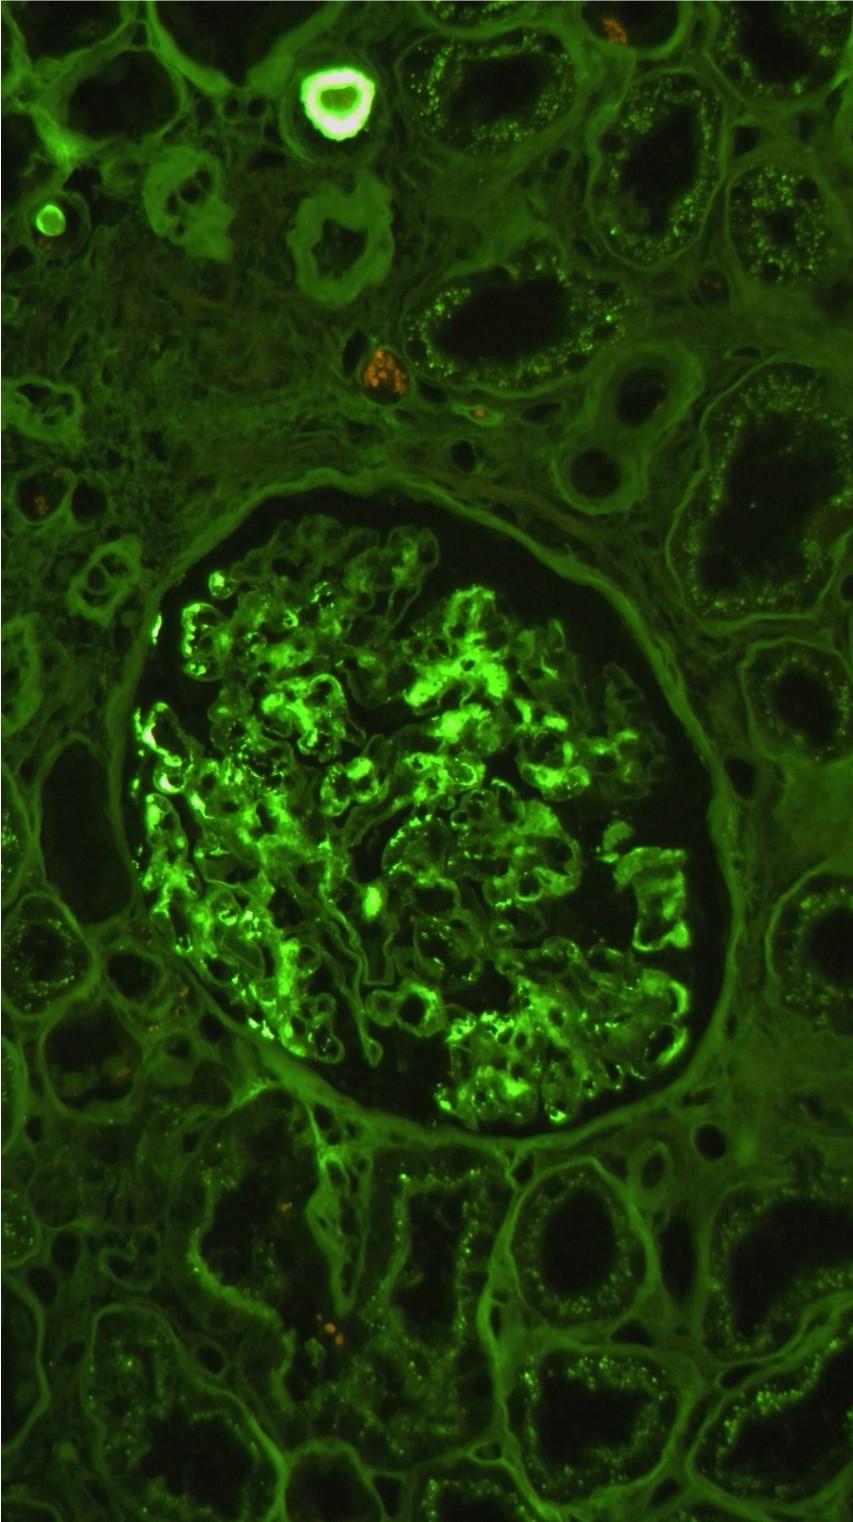

IF – Granular capillary deposits EM – Subepithelial Hump-like deposits

■ IF / IP will show chunky, granular IgG and C3 deposits in the capillary walls

■ EM will show subepithelial hump-like electron dense deposits on the capillary walls